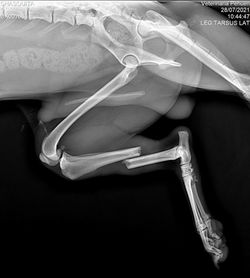

Poseemos un Equipo de Rayos X, Italiano modelo Isomedic PX 100 y un digitalizador C-R AGFA de última tecnología. Estos equipos nos permite mejorar la calidad de las imágenes radiológicas, con lo que podemos realizar mejores diagnósticos. Por otra parte, los aparatos están especialmente diseñados para su uso en Medicina Veterinaria, lo que nos da una amplia gama de posibilidades radiológicas, abarcando desde pequeños animales exóticos hasta grandes perros, a los que otros equipos no tienen la capacidad de realizar buenas imágenes. Junto con lo anterior, y no menos importante podemos señalar que poseemos una sala de rayos completamente plomada y autorizada por la autoridad sanitaria, autorización que nos distingue a nivel nacional.